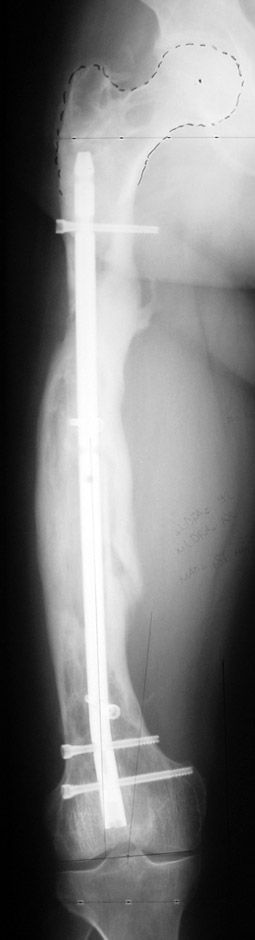

The duration of external fixation (external fixation index) depends on the amount of distraction required, and the extremity is prone to complications during this period. After the distraction phase is completed, the external fixator remains in place during the consolidation phase, which lasts twice as long as the distraction phase; but this period is hardly tolerated. If the external fixator is removed before sufficient consolidation is achieved, fractures, deformity and shortness will be the result. In our department, ‘lenghthening over nail’ method is used in order to decrease the external fixation index and increase patient comfort and activity level. In this method, the intramedullary nail is statically locked after the completion of the distraction phase, and external fixator is removed. The extremity is stabilized by the intramedullary nail during consolidation phase. In this way, complications due to long external fixation index or early removal of the external fixator are avoided.